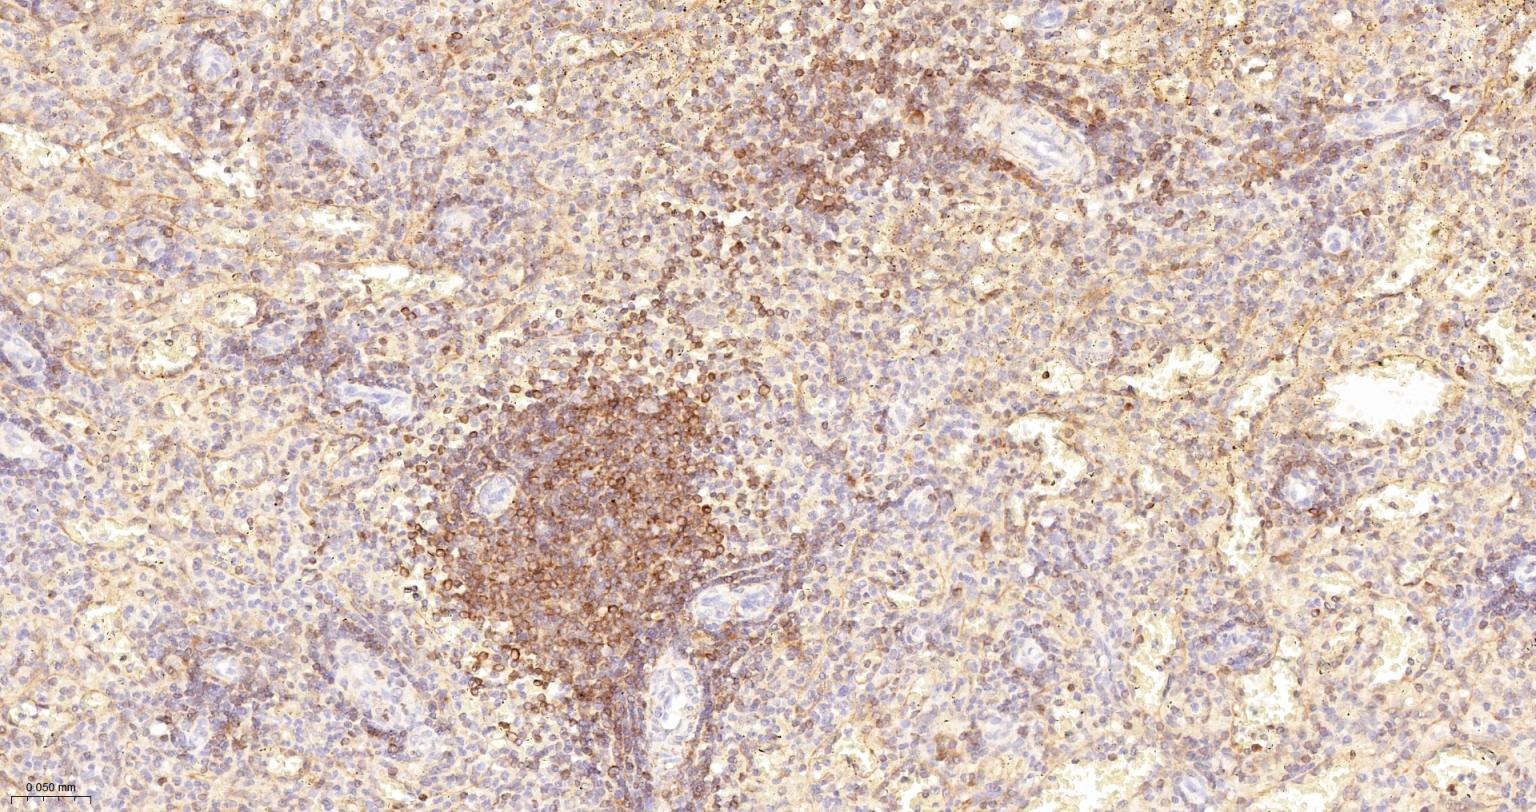

Paraformaldehyde-fixed, paraffin embedded Mouse Lymph; Antigen retrieval by boiling in sodium citrate buffer (pH6.0) for 15 min; The section was incubated with Bcl-2 Monoclonal Antibody, Unconjugated (bsm-61074R) at 1:200 overnight at 4°C, followed by conjugation to the bs-0295G-HRP and DAB (C-0010) staining.

Paraformaldehyde-fixed, paraffin embedded Human Lymph; Antigen retrieval by boiling in sodium citrate buffer (pH6.0) for 15 min; Antibody incubation with Bcl-2 Monoclonal Antibody, Unconjugated(bsm-61074R) at 1:200 overnight at 4°C, followed by conjugation to the SP Kit (Rabbit, SP-0023)and DAB (C-0010) staining.

Paraformaldehyde-fixed, paraffin embedded Human Tonsil; Antigen retrieval by boiling in sodium citrate buffer (pH6.0) for 15 min; Antibody incubation with Bcl-2 Monoclonal Antibody, Unconjugated(bsm-61074R) at 1:200 overnight at 4°C, followed by conjugation to the SP Kit (Rabbit, SP-0023)and DAB (C-0010) staining.

Paraformaldehyde-fixed, paraffin embedded Human Spleen; Antigen retrieval by boiling in sodium citrate buffer (pH6.0) for 15 min; Antibody incubation with Bcl-2 Monoclonal Antibody, Unconjugated(bsm-61074R) at 1:200 overnight at 4°C, followed by conjugation to the SP Kit (Rabbit, SP-0023)and DAB (C-0010) staining.

Paraformaldehyde-fixed, paraffin embedded Mouse Spleen; Antigen retrieval by boiling in sodium citrate buffer (pH6.0) for 15 min; Antibody incubation with Bcl-2 Monoclonal Antibody, Unconjugated(bsm-61074R) at 1:200 overnight at 4°C, followed by conjugation to the SP Kit (Rabbit, SP-0023)and DAB (C-0010) staining.